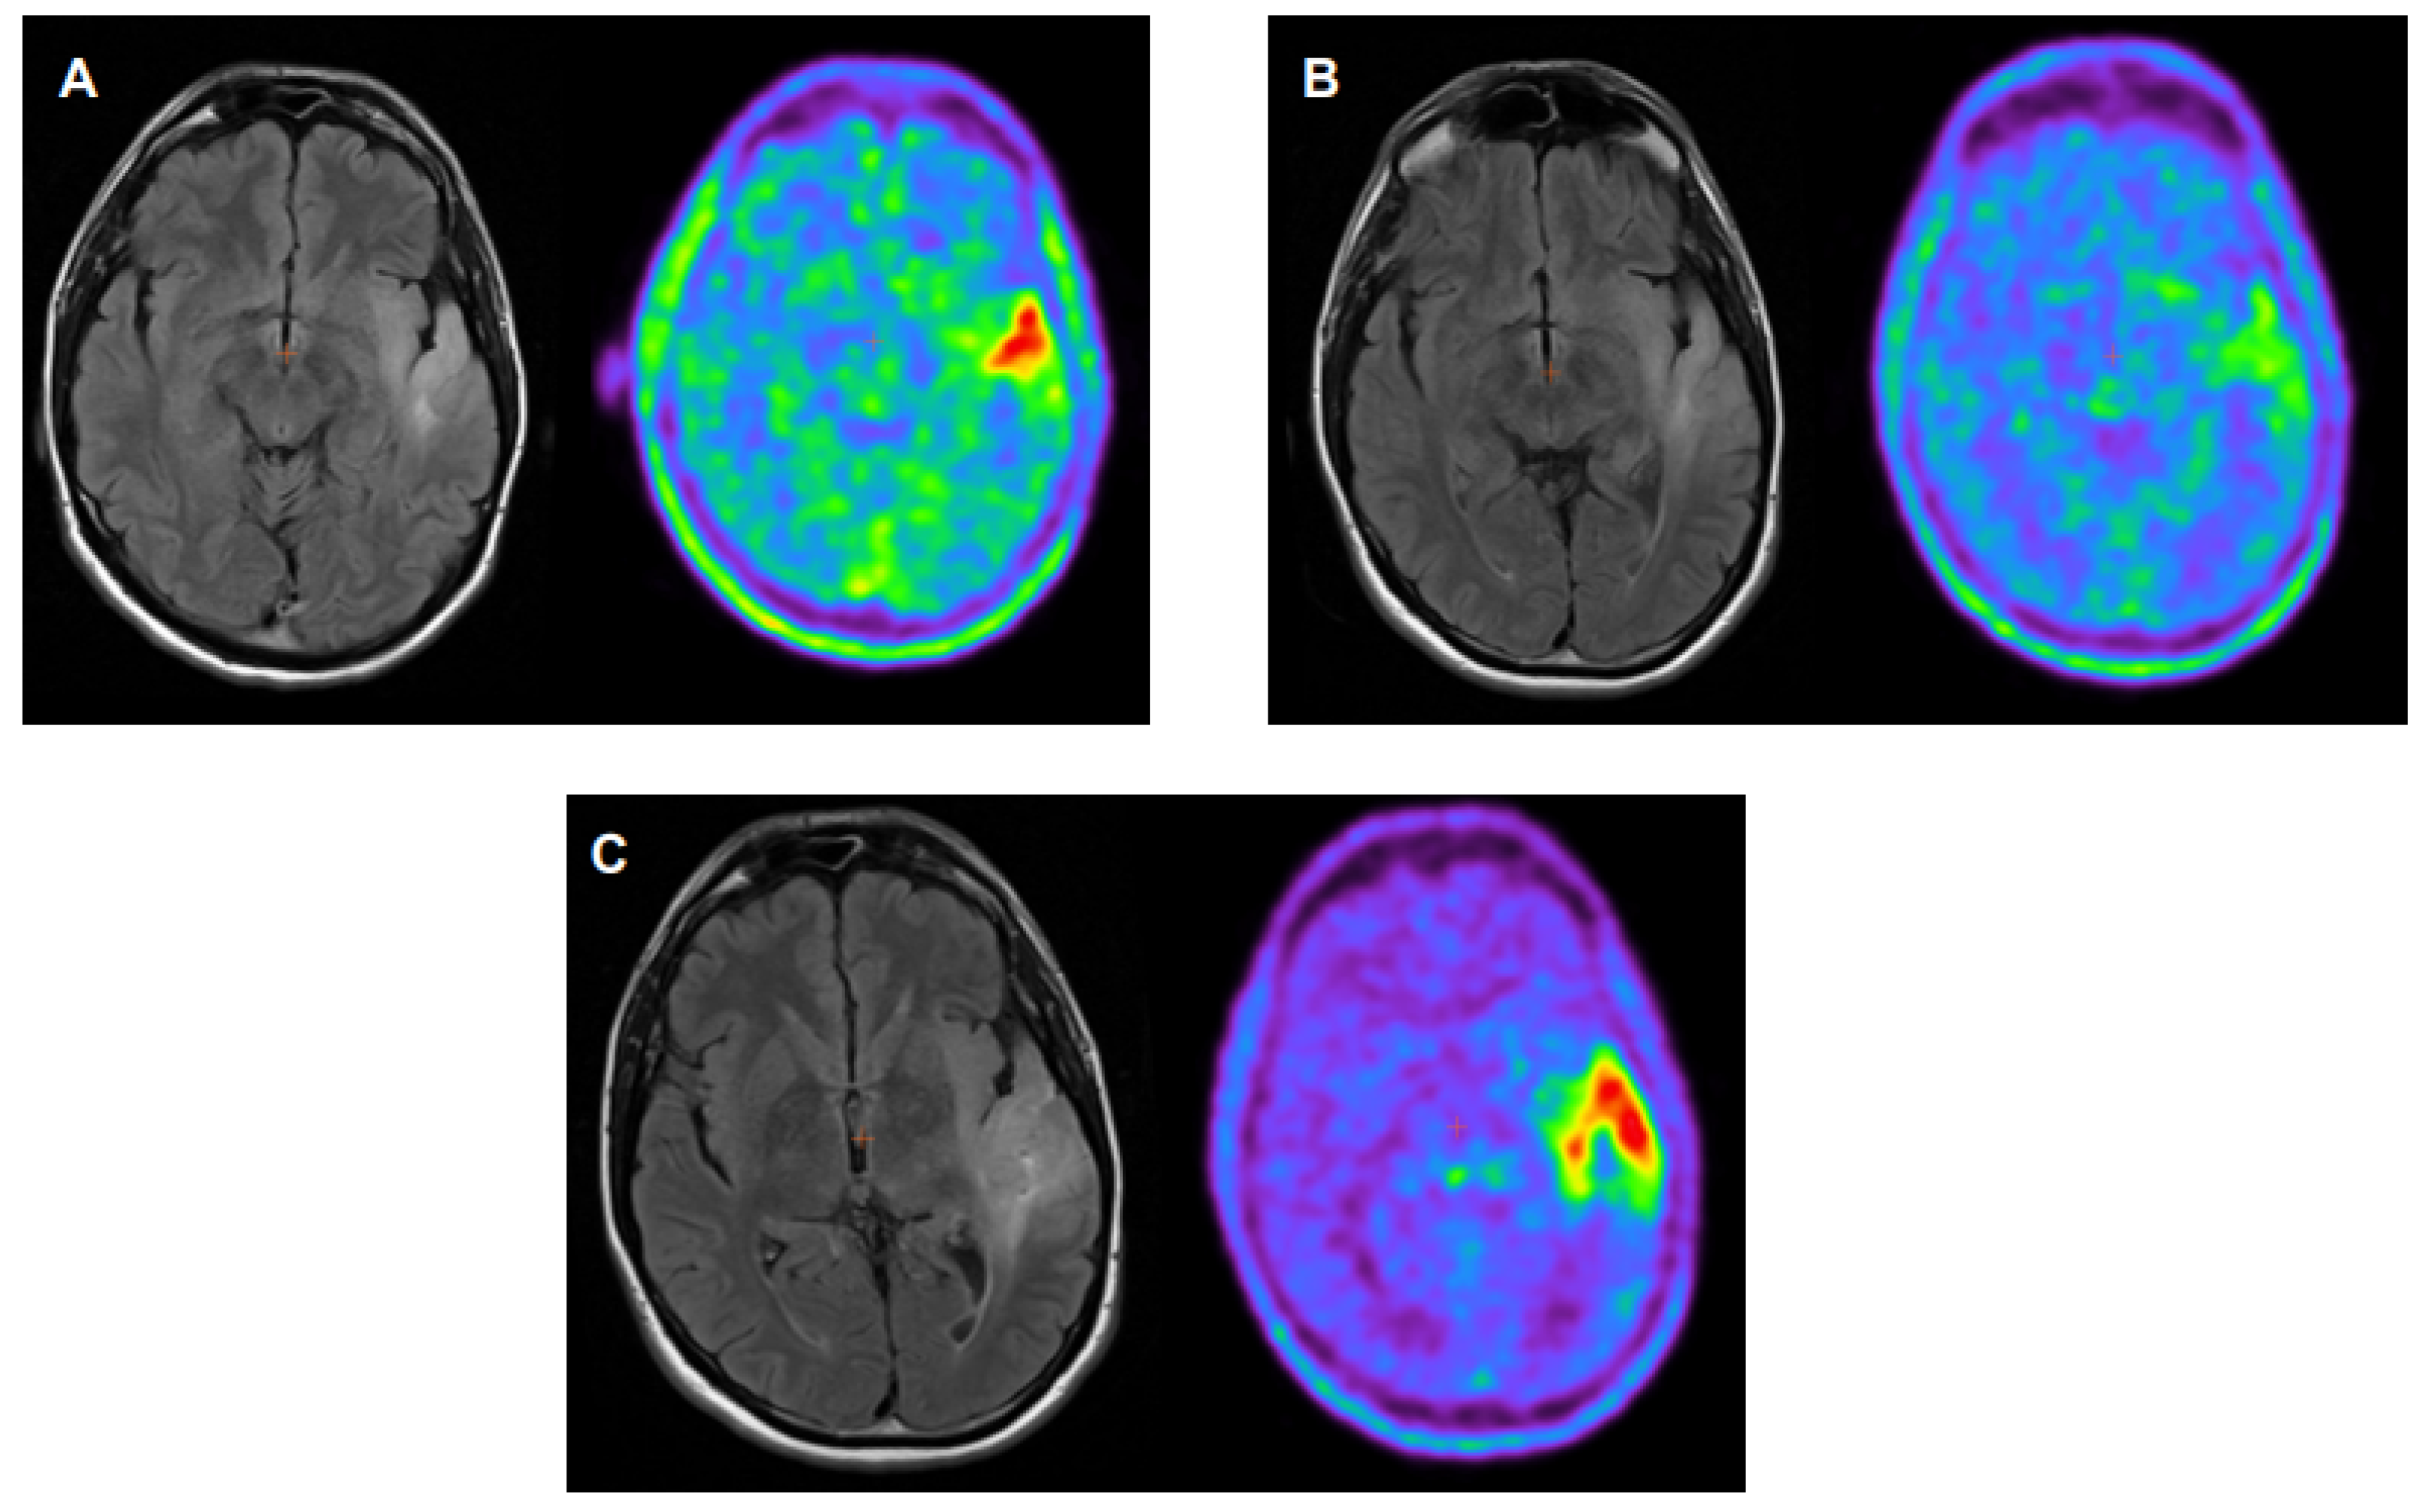

- Galldiks, N.; Dunkl, V.; Ceccon, G.; Tscherpel, C.; Stoffels, G.; Law, I.; Henriksen, O.M.; Muhic, A.; Poulsen, H.S.; Steger, J.; et al. Early treatment response evaluation using FET PET compared to MRI in glioblastoma patients at first progression treated with bevacizumab plus lomustine. Eur. J. Nucl. Med. Mol. Imaging 2018, 45, 2377–2386. [Google Scholar] [CrossRef]

- Galldiks, N.; Rapp, M.; Stoffels, G.; Fink, G.R.; Shah, N.J.; Coenen, H.H.; Sabel, M.; Langen, K.J. Response assessment of bevacizumab in patients with recurrent malignant glioma using [18F]Fluoroethyl-L-tyrosine PET in comparison to MRI. Eur. J. Nucl. Med. Mol. Imaging 2013, 40, 22–33. [Google Scholar] [CrossRef]

- Hutterer, M.; Nowosielski, M.; Putzer, D.; Waitz, D.; Tinkhauser, G.; Kostron, H.; Muigg, A.; Virgolini, I.J.; Staffen, W.; Trika, E.; et al. O-(2-18F-fluoroethyl)-L tyrosine PET predicts failure of antiangiogenic treatment in patients with recurrent high-grade glioma. J. Nucl. Med. 2011, 52, 856–864. [Google Scholar] [CrossRef]